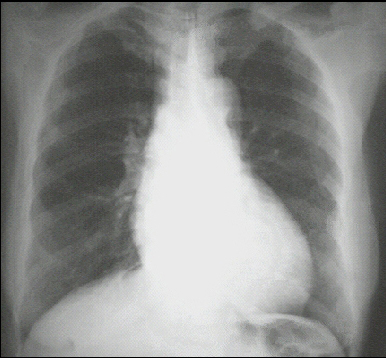

These chest X rays show left ventricular enlargement and a dilated aorta. The PA view demonstrates cardiomegaly, as evidenced by a cardiothoracic ratio greater than 50%. Note also the increased inferolateral cardiac border that is consistent with ventricular enlargement due to volume overload. The ascending, transverse, and descending aortic shadows are also prominent.

The lateral view shows left ventricular enlargement, as evidenced by posterior displacement of the left ventricular shadow.